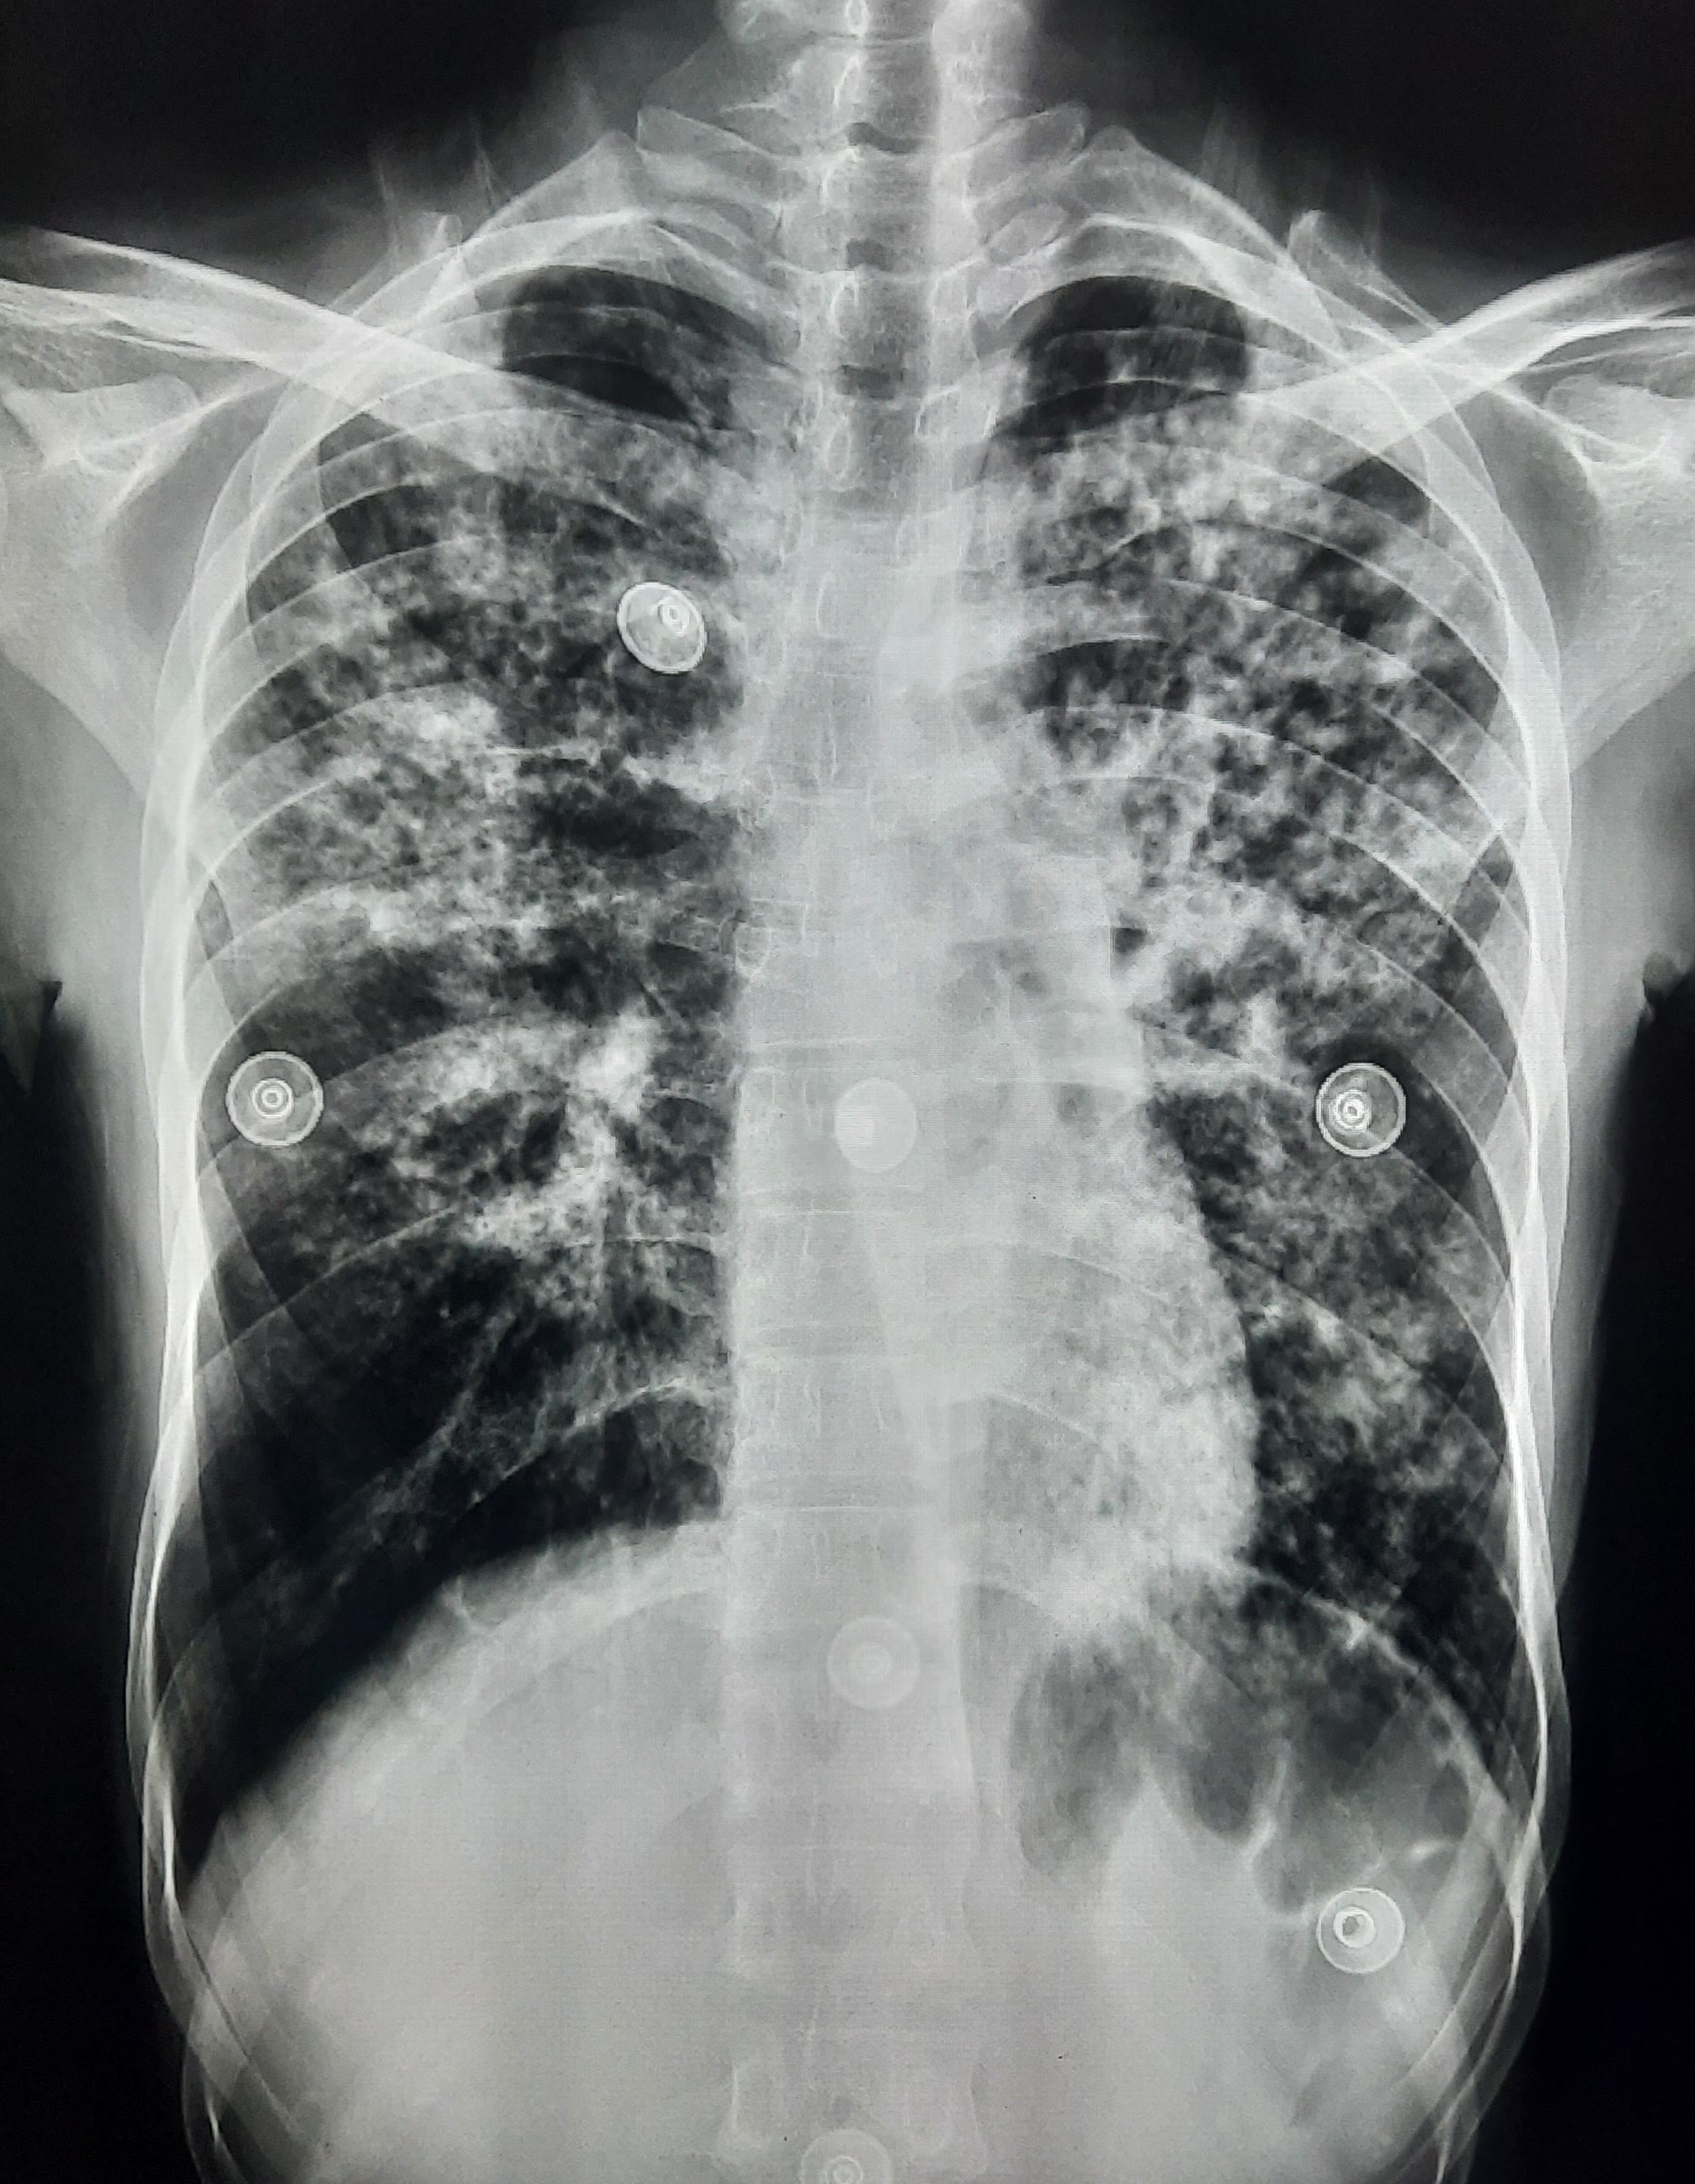

| 138 | IGGMC, Nagpur, Nagpur | P2 | 29-4334 | Rohit Gijre | Consent taken on Paper | 25 Yrs. |

Provisional Diag : Clinically Diagnosed Bilateral Plural Effusion

Final Diag : Tubercular Pleural effusion (Clinically Diagnosed Tubercular Pleural effusion) |

TB Case (Confirmed) | Multiple Right Side With Bilateral Infiltration | Abnormality visible on x-ray |